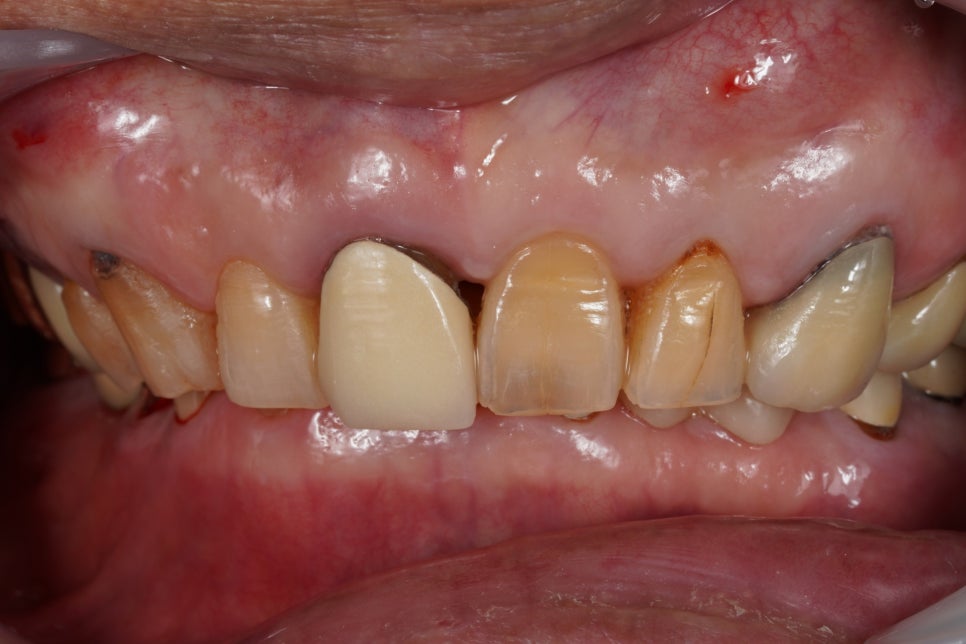

크라운 내부 치아가 변색된 경우

문제는 혈관과 신경을 모두 제거하기 때문에 내부 구조가 수분을 잃고 유기물이 변성되면서 투명도를 잃게 돼요.

그러면 치아 내부 색이 회색이나 검은색처럼 어두워지기도 하죠. 겉에는 크라운이 씌워져 있어서 멀쩡해 보이는데 오래되면서 잇몸이 조금씩 퇴축되면 경계 부분에서 검게 비쳐 보이게 되는 거죠.

검게 보이는 경계 부위